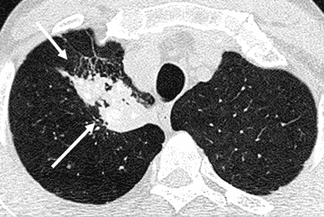

Texto alternativo para a imagem Figura 1 - Créditos: Dra Elazir Mota - Rio de Janeiro/RJ

Descrição da lesão: Tomografia computadorizada de tórax sem a administração do contraste. Grandes opacidades nas regiões posteriores dos lobos superiores, associadas à distorção arquitetural do parênquima. Observam-se ainda calcificações no interior das opacidades pulmonares (setas brancas - figuras 1 e 2).